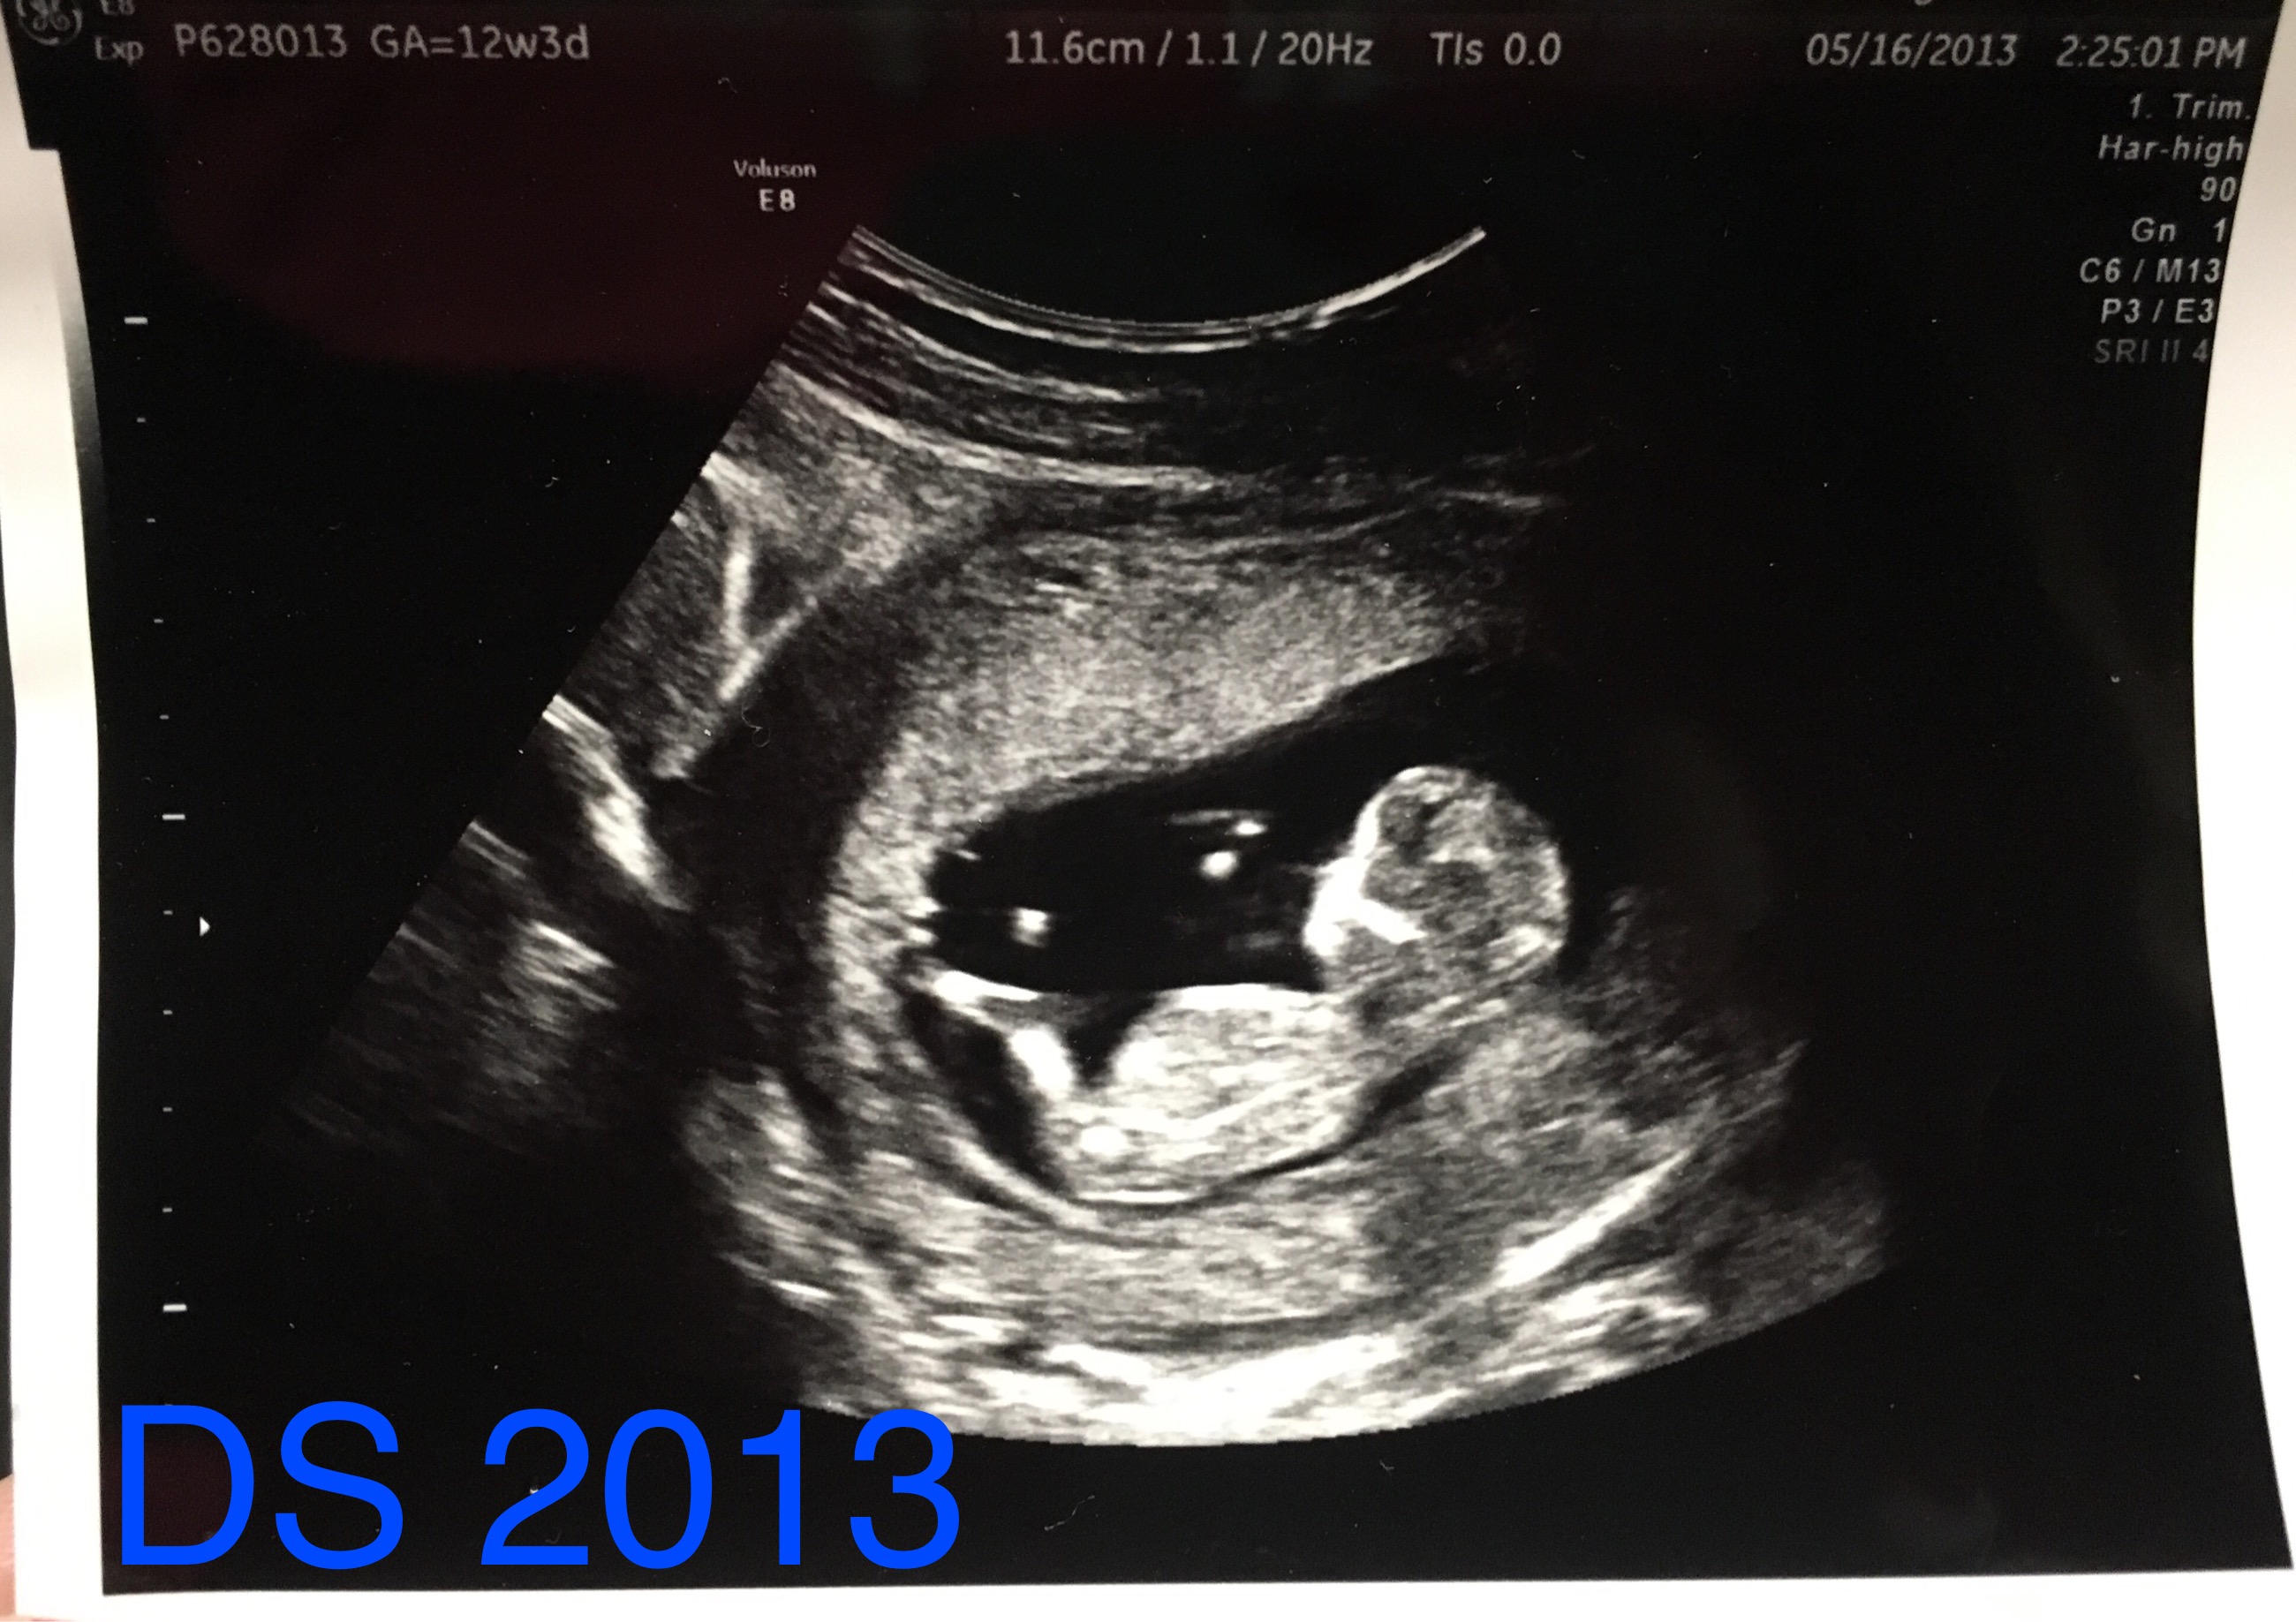

Below are my 12+4 week scan shots, I'm hoping for some gender guesses. Is the nub even visible? I've looked at tons of pics online and can't seem to make out the nub in my pic. I'm kind of thinking boy, this bub looks so much like my DS around the same time (in regards to skull shape, although this baby has a flatter face). I've attached pics of DS as well.

And here is DS 1:

Attachment 29172